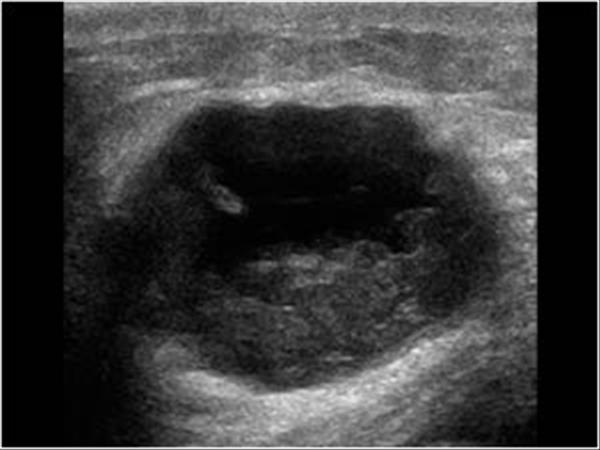

Ung thư vú - Ảnh 4

Ung thư vú

» Thông tin: Nữ giới – 82 tuổi.

» Lâm sàng: Khối tuyến vú.